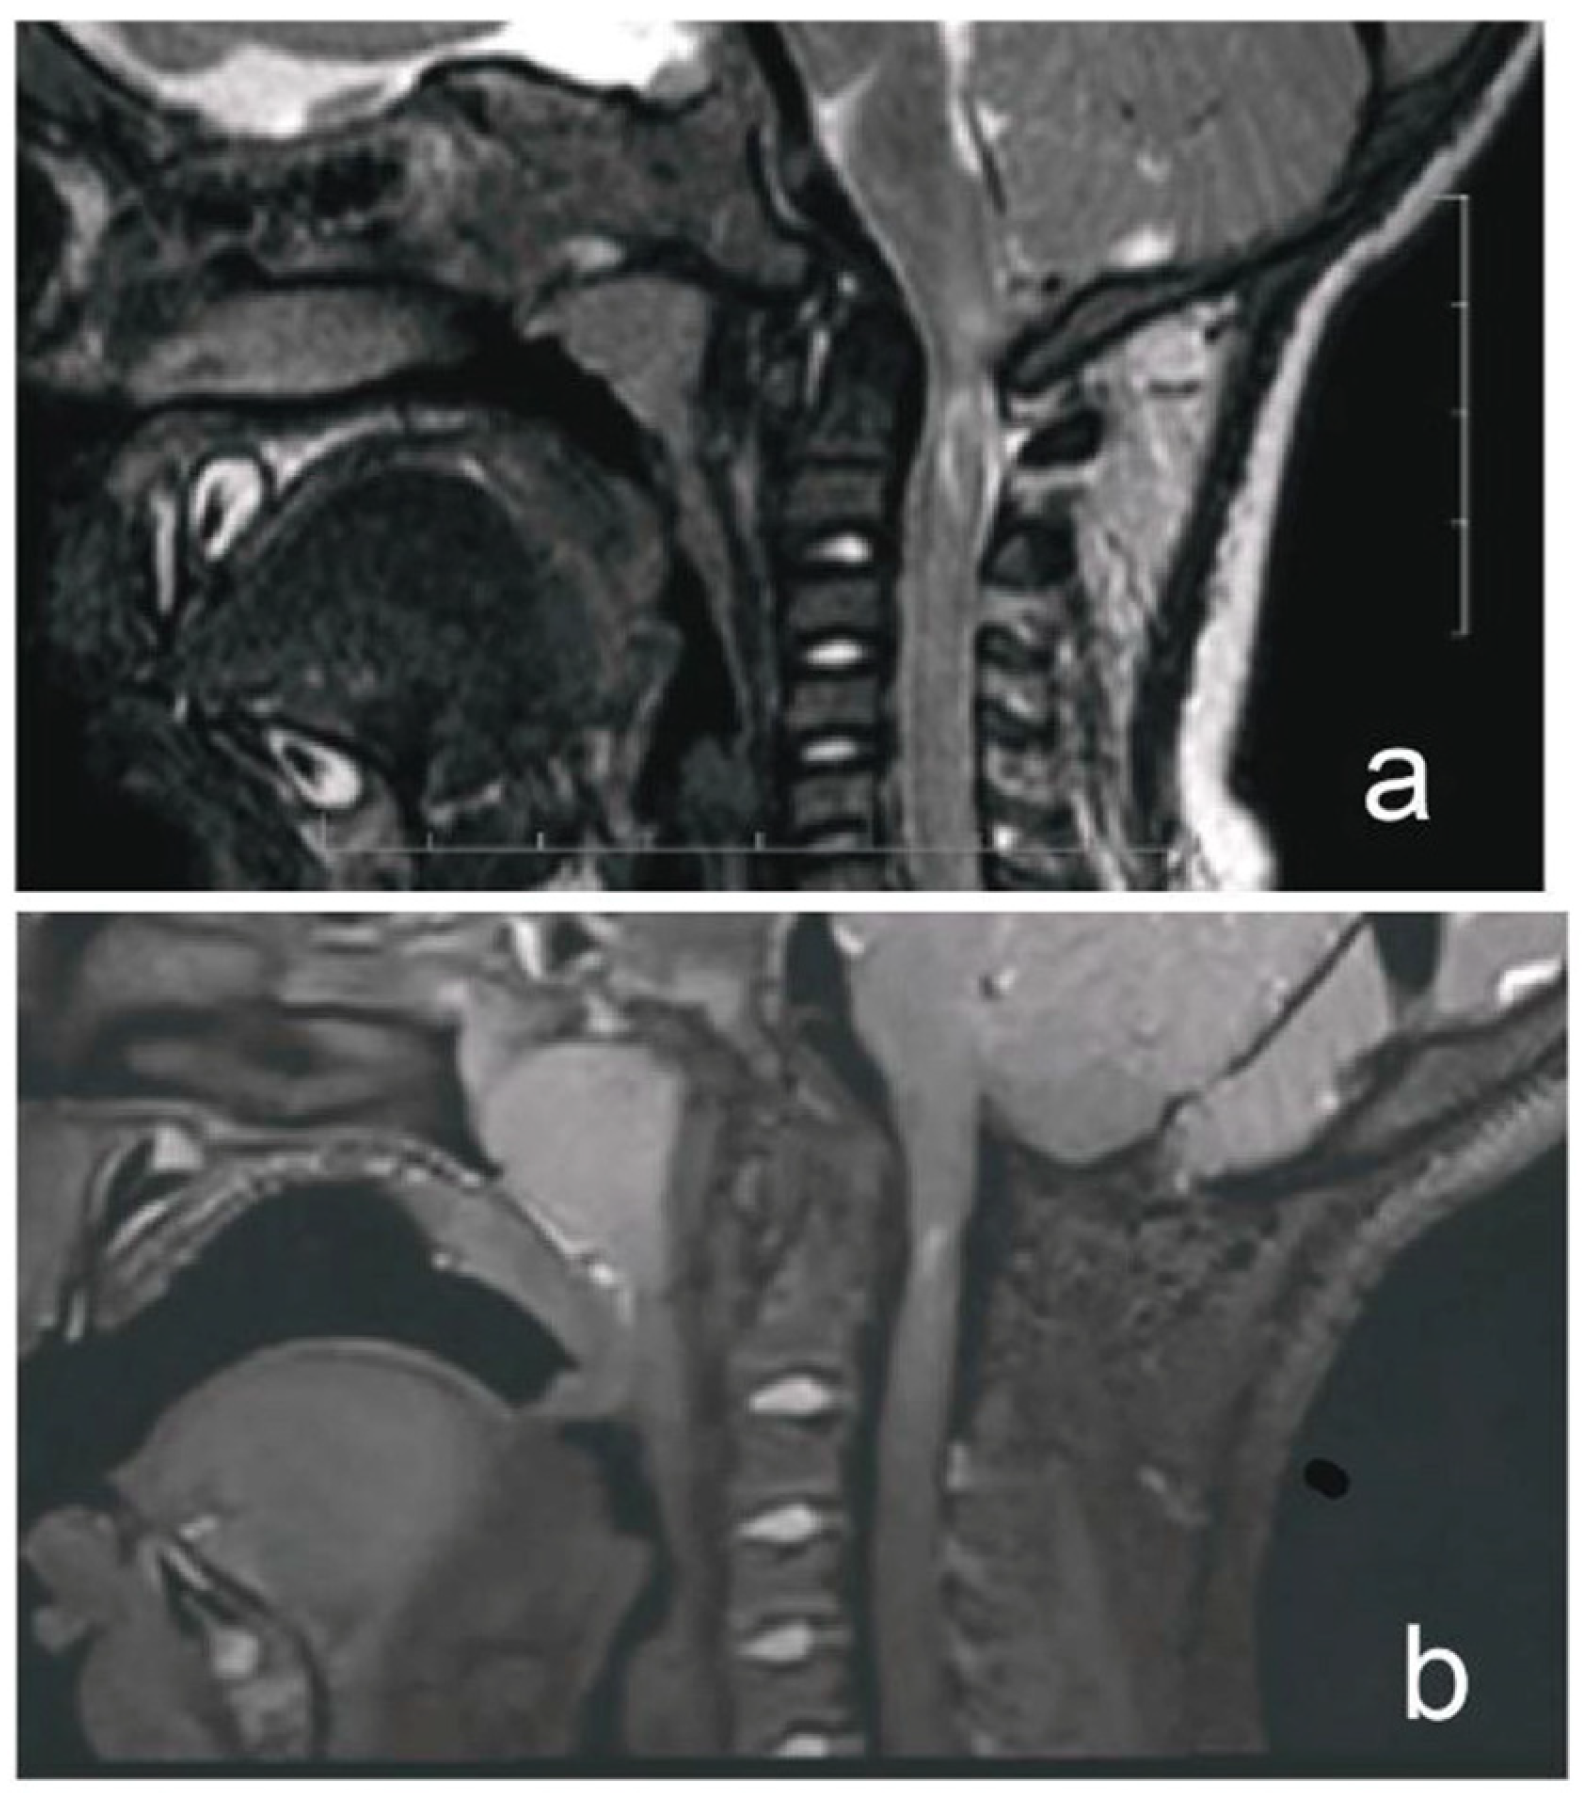

A 1-year-old boy with achondroplasia, measuring 71 cm in height and 8400 g in weight, experienced a whiplash injury. The mechanism of injury was described as follows: “After the mother threw the child up in the air and caught him, his head jerked violently, following which he became motionless”. The patient was regularly monitored for achondroplasia at another medical center without any mention of foramen magnum stenosis. Upon admission, the patient presented with signs of achondroplasia, including macrocephaly, a depressed nasal bridge, and a large fontanel measuring 2 × 2 cm. At birth, the patient’s head circumference was 39 cm, and it was 51 cm at the time of admission. A neurological examination revealed acute flaccid tetraparesis with a Medical Research Council (MRC) grade 1/5 in the upper extremities and MRC grades 2–3 in the lower extremities. No other neurological deficits were observed. Initial craniocervical computed tomography demonstrated a reduced volume of the posterior fossa, foramen magnum stenosis, and ventriculomegaly, without any fractures or dislocations (Figure 1a,b). However, magnetic resonance imaging (MRI) revealed foramen magnum stenosis and pathological signal changes in the medulla oblongata, cervical spinal cord in segments C1 and C2, and the posterior atlantoaxial ligament. Additionally, morphological changes in the skull base and basilar impressions were observed (Figure 2a). The patient was monitored in the PICU and experienced an episode of hypoxemia, with an oxygen saturation of 79% on the first night after the injury. This episode resolved spontaneously after administering oxygen through a face mask for 10 min at a rate of 3 L/min. The patient remained respiratory and hemodynamically stable and did not experience any complications. He was breastfed and exhibited no swallowing disorders. Symptomatic treatment included regular analgesia with metamizole, supplemented by rectally administered paracetamol and the use of a soft cervical collar. The neurosurgeon recommended delaying the surgical therapy based on established principles to minimize the risk of intraoperative lesioning of compressed neural structures during the acute phase of the injury and to allow sufficient time for the edema-related compression of neural tissues to subside. A gradual remission of neurological symptoms was observed, and a microsurgical decompression was finally performed two weeks after the injury, after the flaccid tetraparesis subsided gradually to a MRC grade of 3/5 for the upper extremities and to an MRC grade of 4/5 for the lower extremities.

Figure 2.

MRI of a child with achondroplasia who sustained a whiplash injury. (a) T2-weighted magnetic resonance image (MRI) of a 1-year-old boy with achondroplasia who developed acute tetraparesis (Medical Research Council grade: 1/5 in the upper extremities, 2–3/5 in the lower extremities) after a whiplash injury, showing foramen magnum stenosis, pathological signal changes in the medulla oblongata, cervical cord in segments C1 and C2, and posterior atlantoaxial ligament. (b) T2-weighted sampling perfection with application of optimized contrast using different flip angle evolution MRI obtained at our hospital 4 years postoperatively demonstrated the disappearance of pathological signal change in the medulla oblongata, a residual area of central hyperintensity in the C1 segment of the cervical cord, as well as a reduced anteroposterior diameter of the cord at this level. There was also a perimedullary flow void signal in the cervicocranial junction, indicating cerebrospinal fluid (CSF) flow.

The patient’s postoperative course was uneventful. The patient was transferred from the PICU to the neurosurgery ward 48 h post-operatively and was discharged from the hospital on day 8. After discharge, the patient wore a soft collar for one month and attended outpatient physiotherapy. Follow-up monitoring was conducted by a pediatric neurosurgeon at our hospital. Tetraparesis gradually improved, and no neurological symptoms were observed at outpatient follow-up 3 months postoperatively. Follow-up T2-weighted sampling perfection with the application of optimized contrast using different flip angle evolution MRI performed 4 years postoperatively revealed resolution of the edema, focal cervical cord atrophy, a small area of central myelomalacia at the C2 level, and a flow void signal, indicating adequate decompression of the craniocervical junction (Figure 2b). The patient then was checked-up on by a pediatric endocrinologist at our center. The timeline of the case is shown in Figure 3.